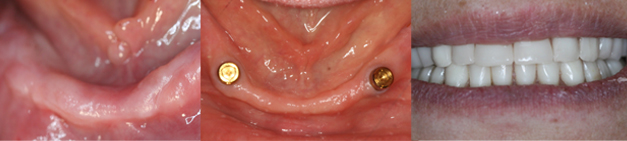

2-4 implants are placed in the lower jaw, 4-6 implants in the upper jaw can support a full denture. This procedure is very economical, greatly improves retention, stability and function. All of these stages can be carried out in the single appointment depending on need and condition of the patient.

IMPLANT SUPPORTED DENTURE

Card image Actual Practice Photographs ©Dr.Pavan Bopanna